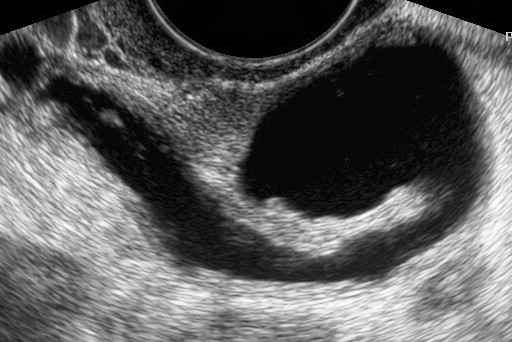

Ин витро е процес, при който се изваждат яйцеклетки от яйчниците на жената, оплождат се от сперматозоиди на мъжа в лабораторни условия, оплодените яйцеклетки се отглеждат няколко дни до развитието на ембриони, които се пренасят в матката на жената.